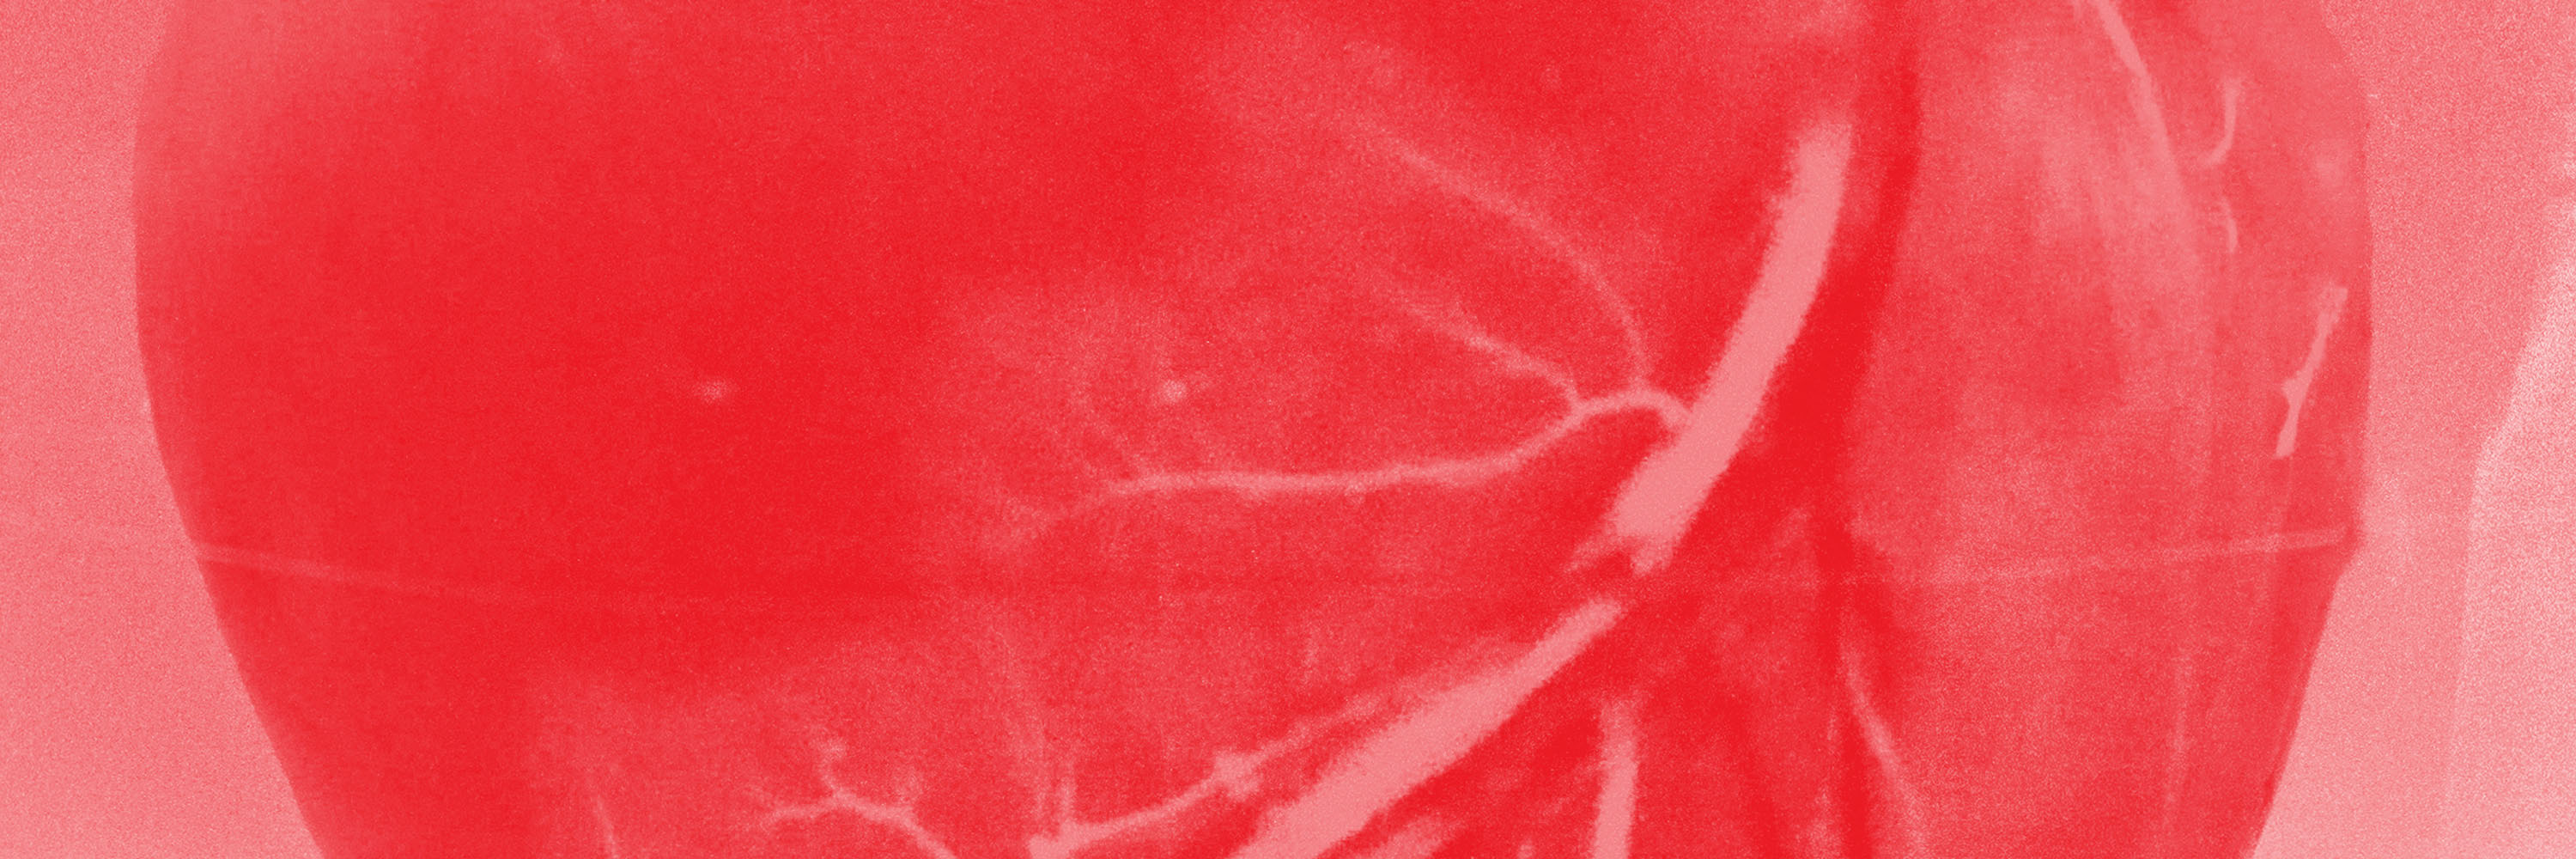

“Pinch-Off Syndrome,” first described by Hinke, is a mechanical complication of totally implantable central venous catheters inserted via subclavian venous access. It occurs when the catheter is compressed between the clavicle and the first rib. Compression can cause transient catheter obstruction and may result in rupture or even complete resection and embolization of the catheter. In this case report, we describe our experience of percutaneous transvenous removal of an embolized port-a-cath fragment within the right heart chambers following a rupture. We used the “retrieval snare” technique and subsequent reimplantation through internal jugular access. The intervention occurred in the same session and involved a multidisciplinary team for a 55-year-old man in need of adjuvant chemotherapy.